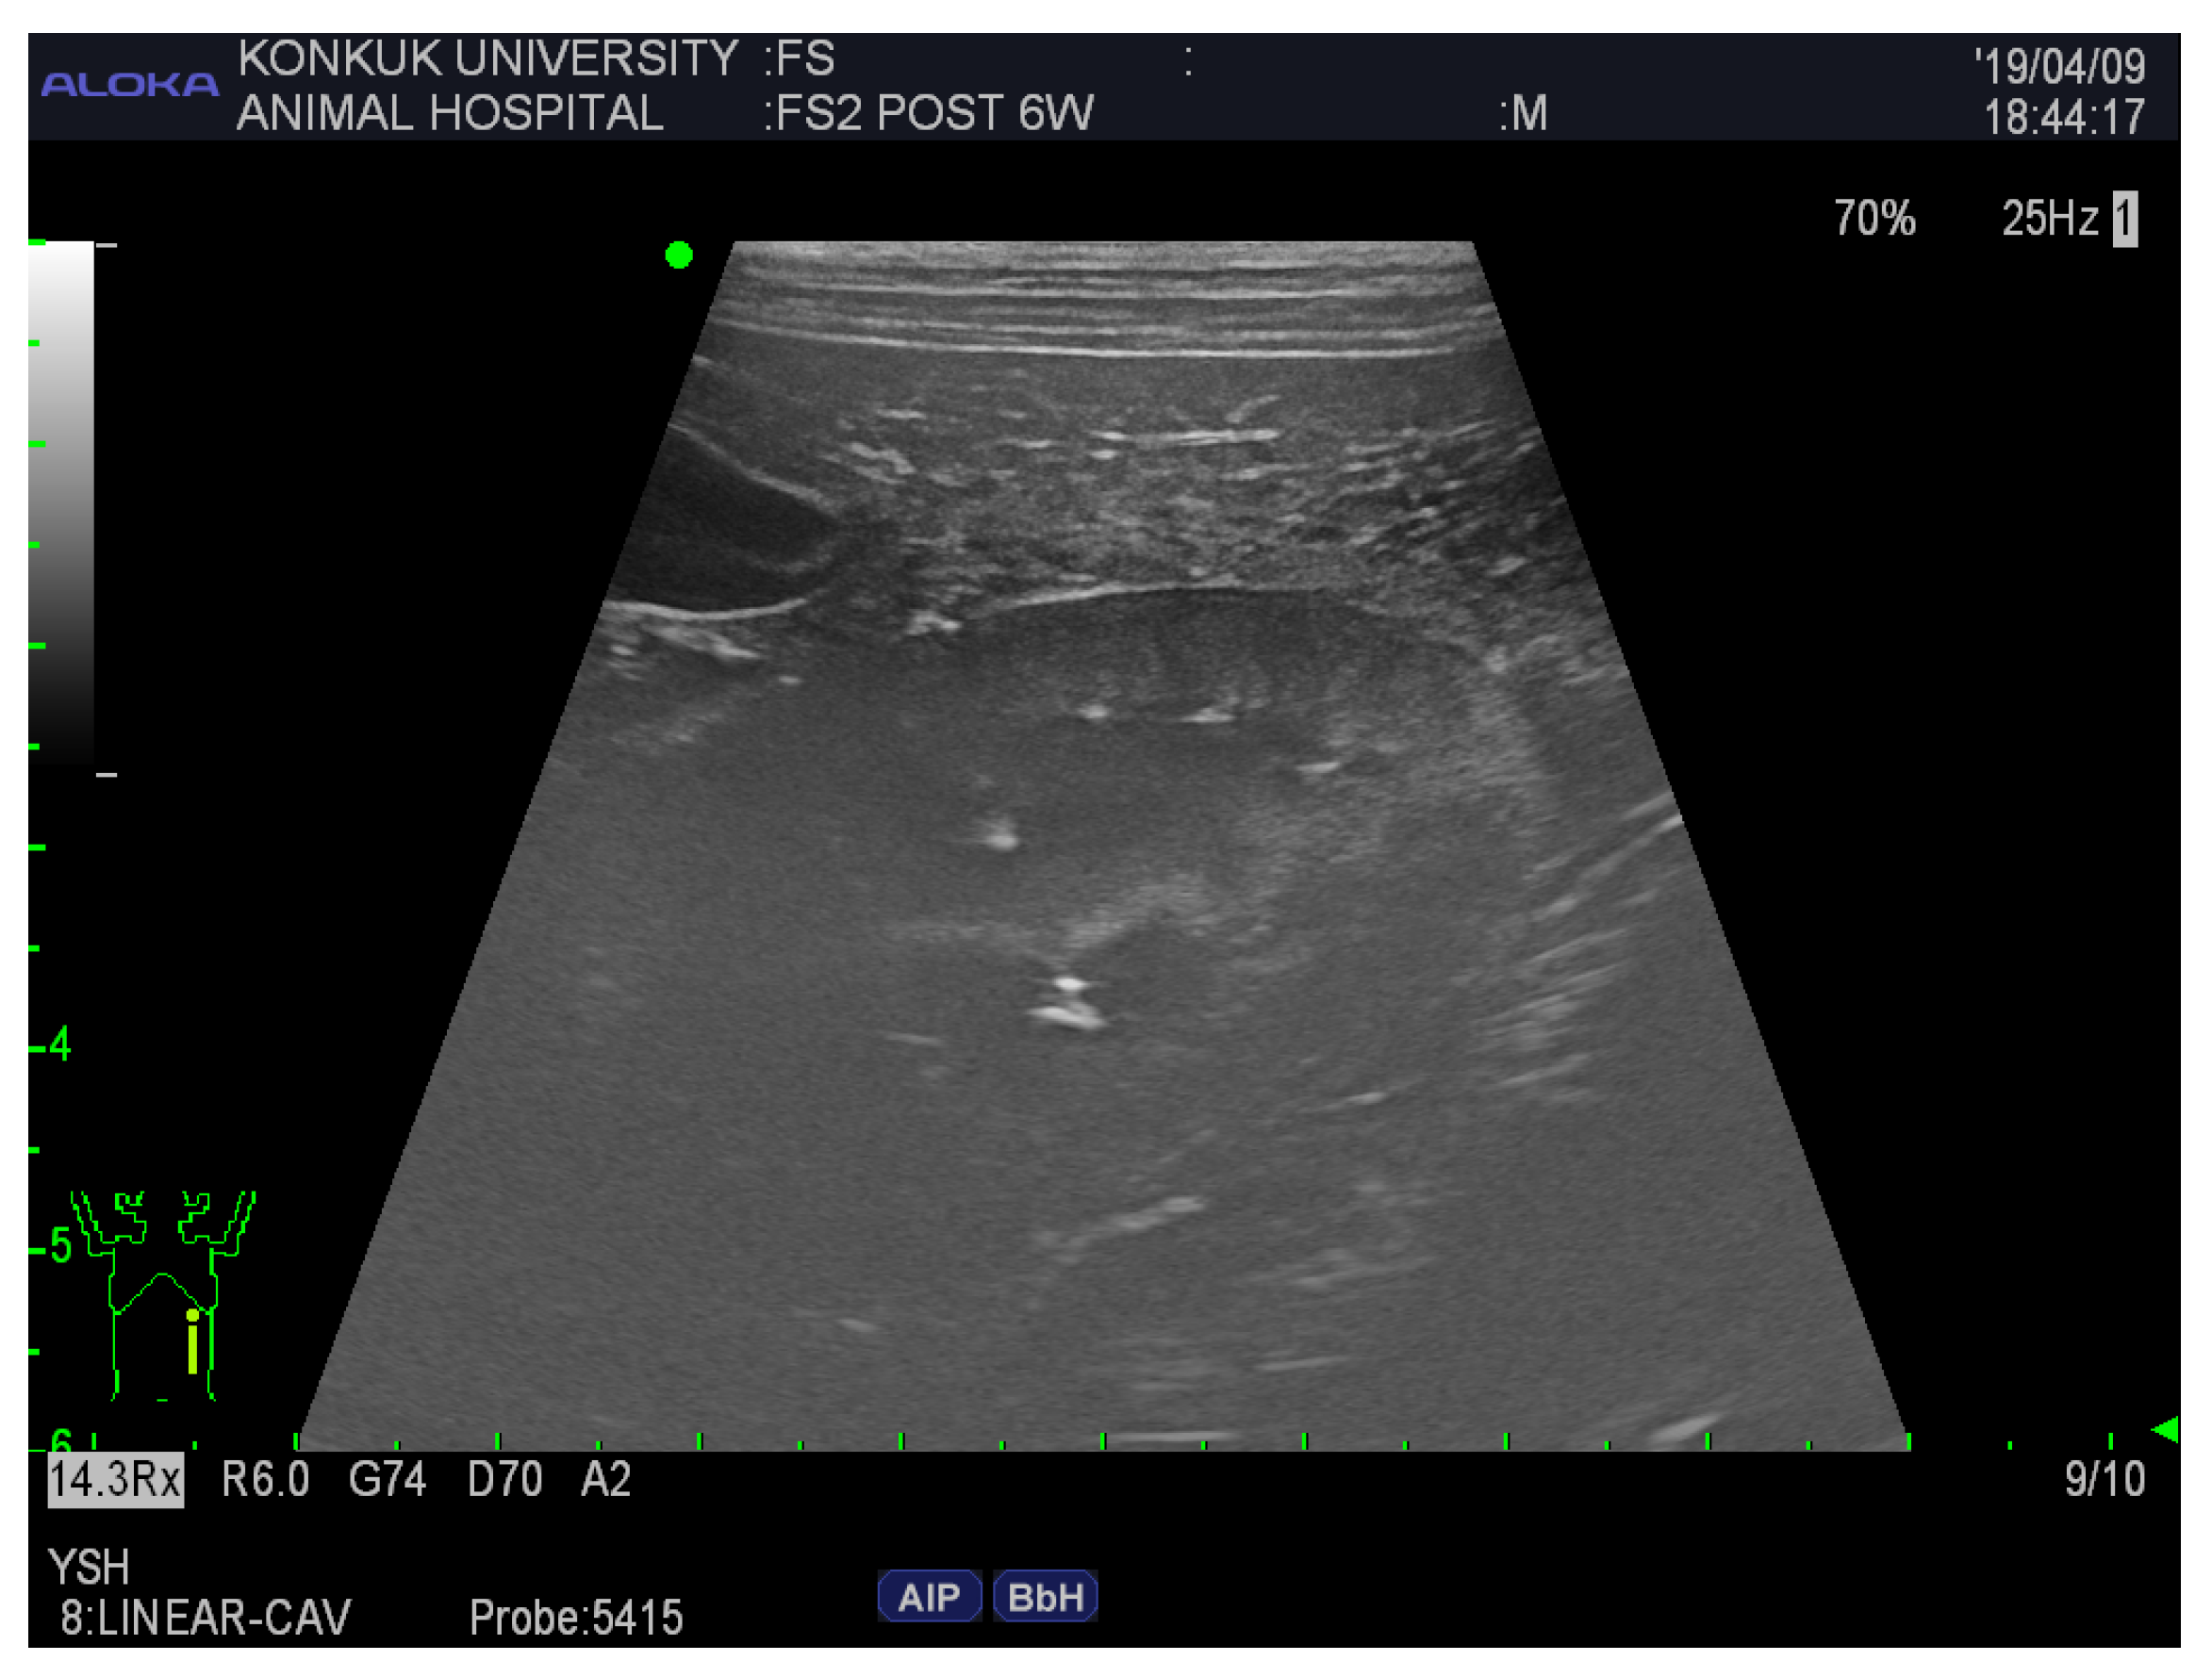

The visibility of the following abdominal organs was scored as follows: liver, distension of the gallbladder, coarse echotexture; spleen, smooth margination, fine echotexture; kidney, both poles visible along the long axis, smooth margination, corticomedullary junction (Figure 2); and the relative echogenicity of the spleen, liver, and kidney.

Figure 2.

Ultrasonographic image of the kidney of an FS cadaver 6 weeks after embalming. The mean score was 2. Both poles at long axis = 1, smooth margination = 3, corticomedullary junction = 2. The scores were assigned as follows; 0 = not visible, 1 = poorly visible, 2 = adequately reproduced, 3 = excellent reproduced.